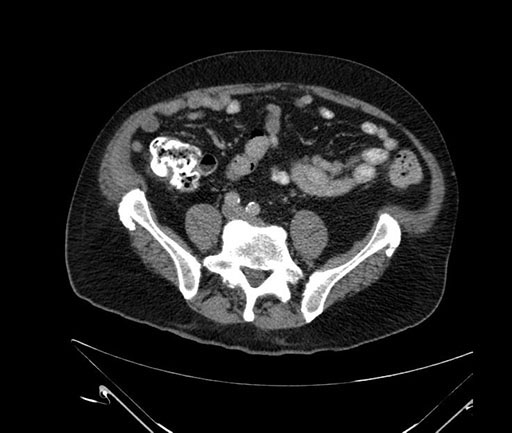

Imaging Analysis

Look through the patient's CT scan to identify any areas of concern for the necessary procedure.

Based on your CT findings, which issue(s) would give reason for "planned slowing down moment(s)" in this case?